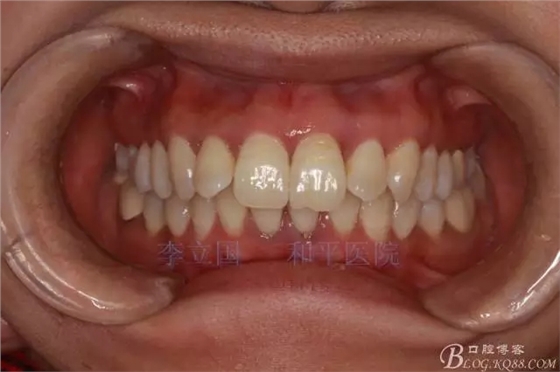

患者主訴前突。

1.患者上前牙直立,面型前突,典型的嘴凸牙不吐,關(guān)鍵是前牙轉(zhuǎn)矩控制,建議使用高轉(zhuǎn)矩托槽。